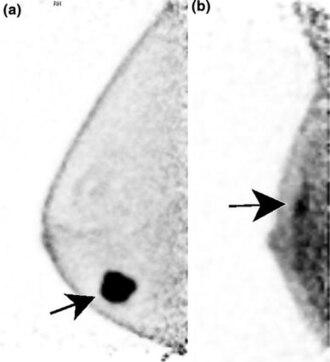

Breast phantom for mammography, ultrasound, and MRI